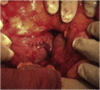

Presentation of case: 75 years old male fell ill with hematemesis, hemohesia and dizziness. Oesophagogastroduodenoscopy (EGD) did not reveal the source of bleeding. Upon admission, a second EGD was performed due to loss of consciousness and anaemia, which revealed only approximate source of bleeding in the third portion of the duodenum. The exact bleeding spot could not be reached and bleeding could not be controlled endoscopically. Patient was transferred to the operating room for an emergency explorative laparotomy. After extensive mobilisation of the duodenum a 2 × 2 cm intraluminal tumour with central bleeding ulceration was found in D3. The diseased part of the duodenum was excised and the duodenotomy was closed with interrupted sutures. Final pathohistological report confirmed gastrointestinal stromal tumour, pT1. Postoperative period was uneventful.